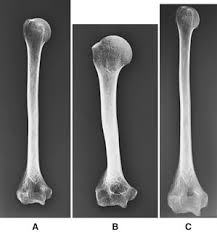

Magnification size distortion is controlled by positioning the body part and x ray tube to diffuse blurring if sufficient magnification is achieved by a reasonable oid and a short sid the object may be visualized as a diffuse gray area.

There are also compromises between noise and other image characteristics such as contrast and blur. It is due to this point source nature that x ray beams will all possess beam divergence. Always place the structure to be examined as close to the film as possible. For this reason the radiographic projection produces a variable degree of distortion.

This should be the greatest distance consistent with the x ray tube output and demands of the procedure with regard to motion control. Définition synonymes citations traduction dans le dictionnaire de la langue française. Angulation of the xray beam the image receptor or the object in relation to the image receptor will all cause some degree of distiortion. Several factors contribute to radiographic distortion whereby the anatomy examined is misrepresenting on the plain radiograph.

Refers to the direction and degree that the tube is moved from its normal position perpendicular to the ir. X rays emerge as a diverging conical beam from the focal spot of the x ray tube. This effect decreases with increased source to object distance relative to the object to film distance and by using a collimator which let through parallel x rays only. Angulation of the x ray tube.